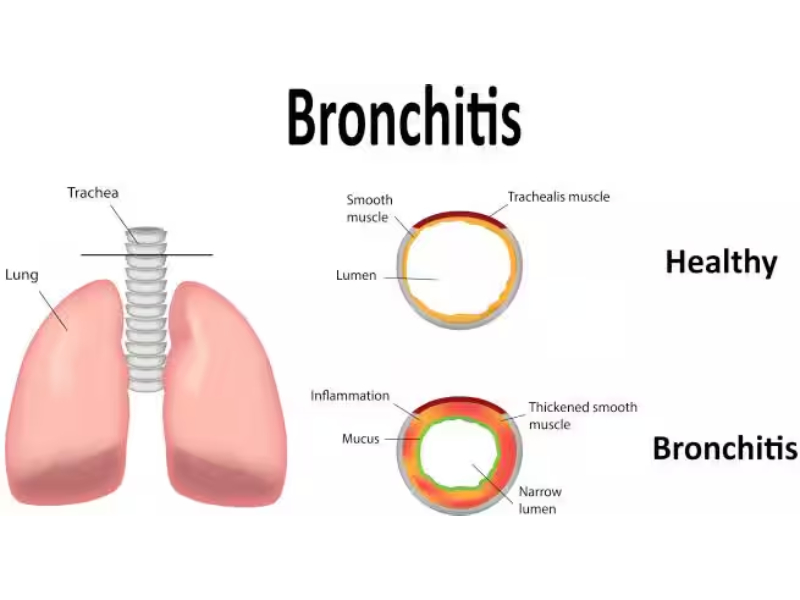

Lung And Other Respiratory Conditions

Lung disease includes many disorders that affect the lungs. Some common lung diseases include asthma, COPD, pneumonia, tuberculosis and lung cancer. Infections like influenza may also affect the lungs and some such diseases can lead to respiratory failure.